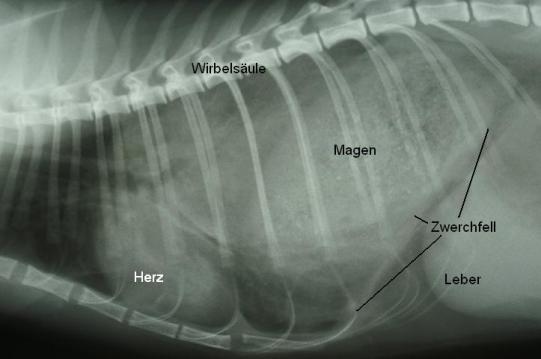

Das Röntgen demonstriert, dass Organe aus der Bauchhöhle (insbesondere der mit Futter gefüllte Magen) in der Brusthöhle liegen. Die Lunge ist dadurch komprimiert, was die verstärkte Atmung erklärt. Diagnose: Zwerchfellsbruch (Diaphragmalhernie). Durch eine (normalerweise nicht existierende) Lücke im Zwerchfell können Organe aus der Bauchhöhle in die Brusthöhle rutschen; diese Lücke kann angeboren oder infolge eines Unfalls entstanden sein. Bei „Malibu“ deutet das plötzliche Auftreten der Atemnot auf eine unfallbedingte Hernie hin.

Die Diaphragmalhernie muss chirurgisch verschlossen werden, da die in der Brusthöhle liegenden Bauchorgane einerseits die Lungenfunktion einschränken und andererseits die Funktion der verlagerten Bauchorgane gestört werden kann (z.B. Verdauungsstörungen).